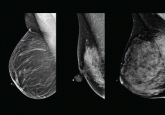

ArticleThe conundrum of explaining breast density to patientsAuthor:Monica Yepes, MDPublish date: December 1, 2013Several states have mandated that, after mammography, patients be informed if their breasts are dense. Explaining what this means is a challenge.Read More